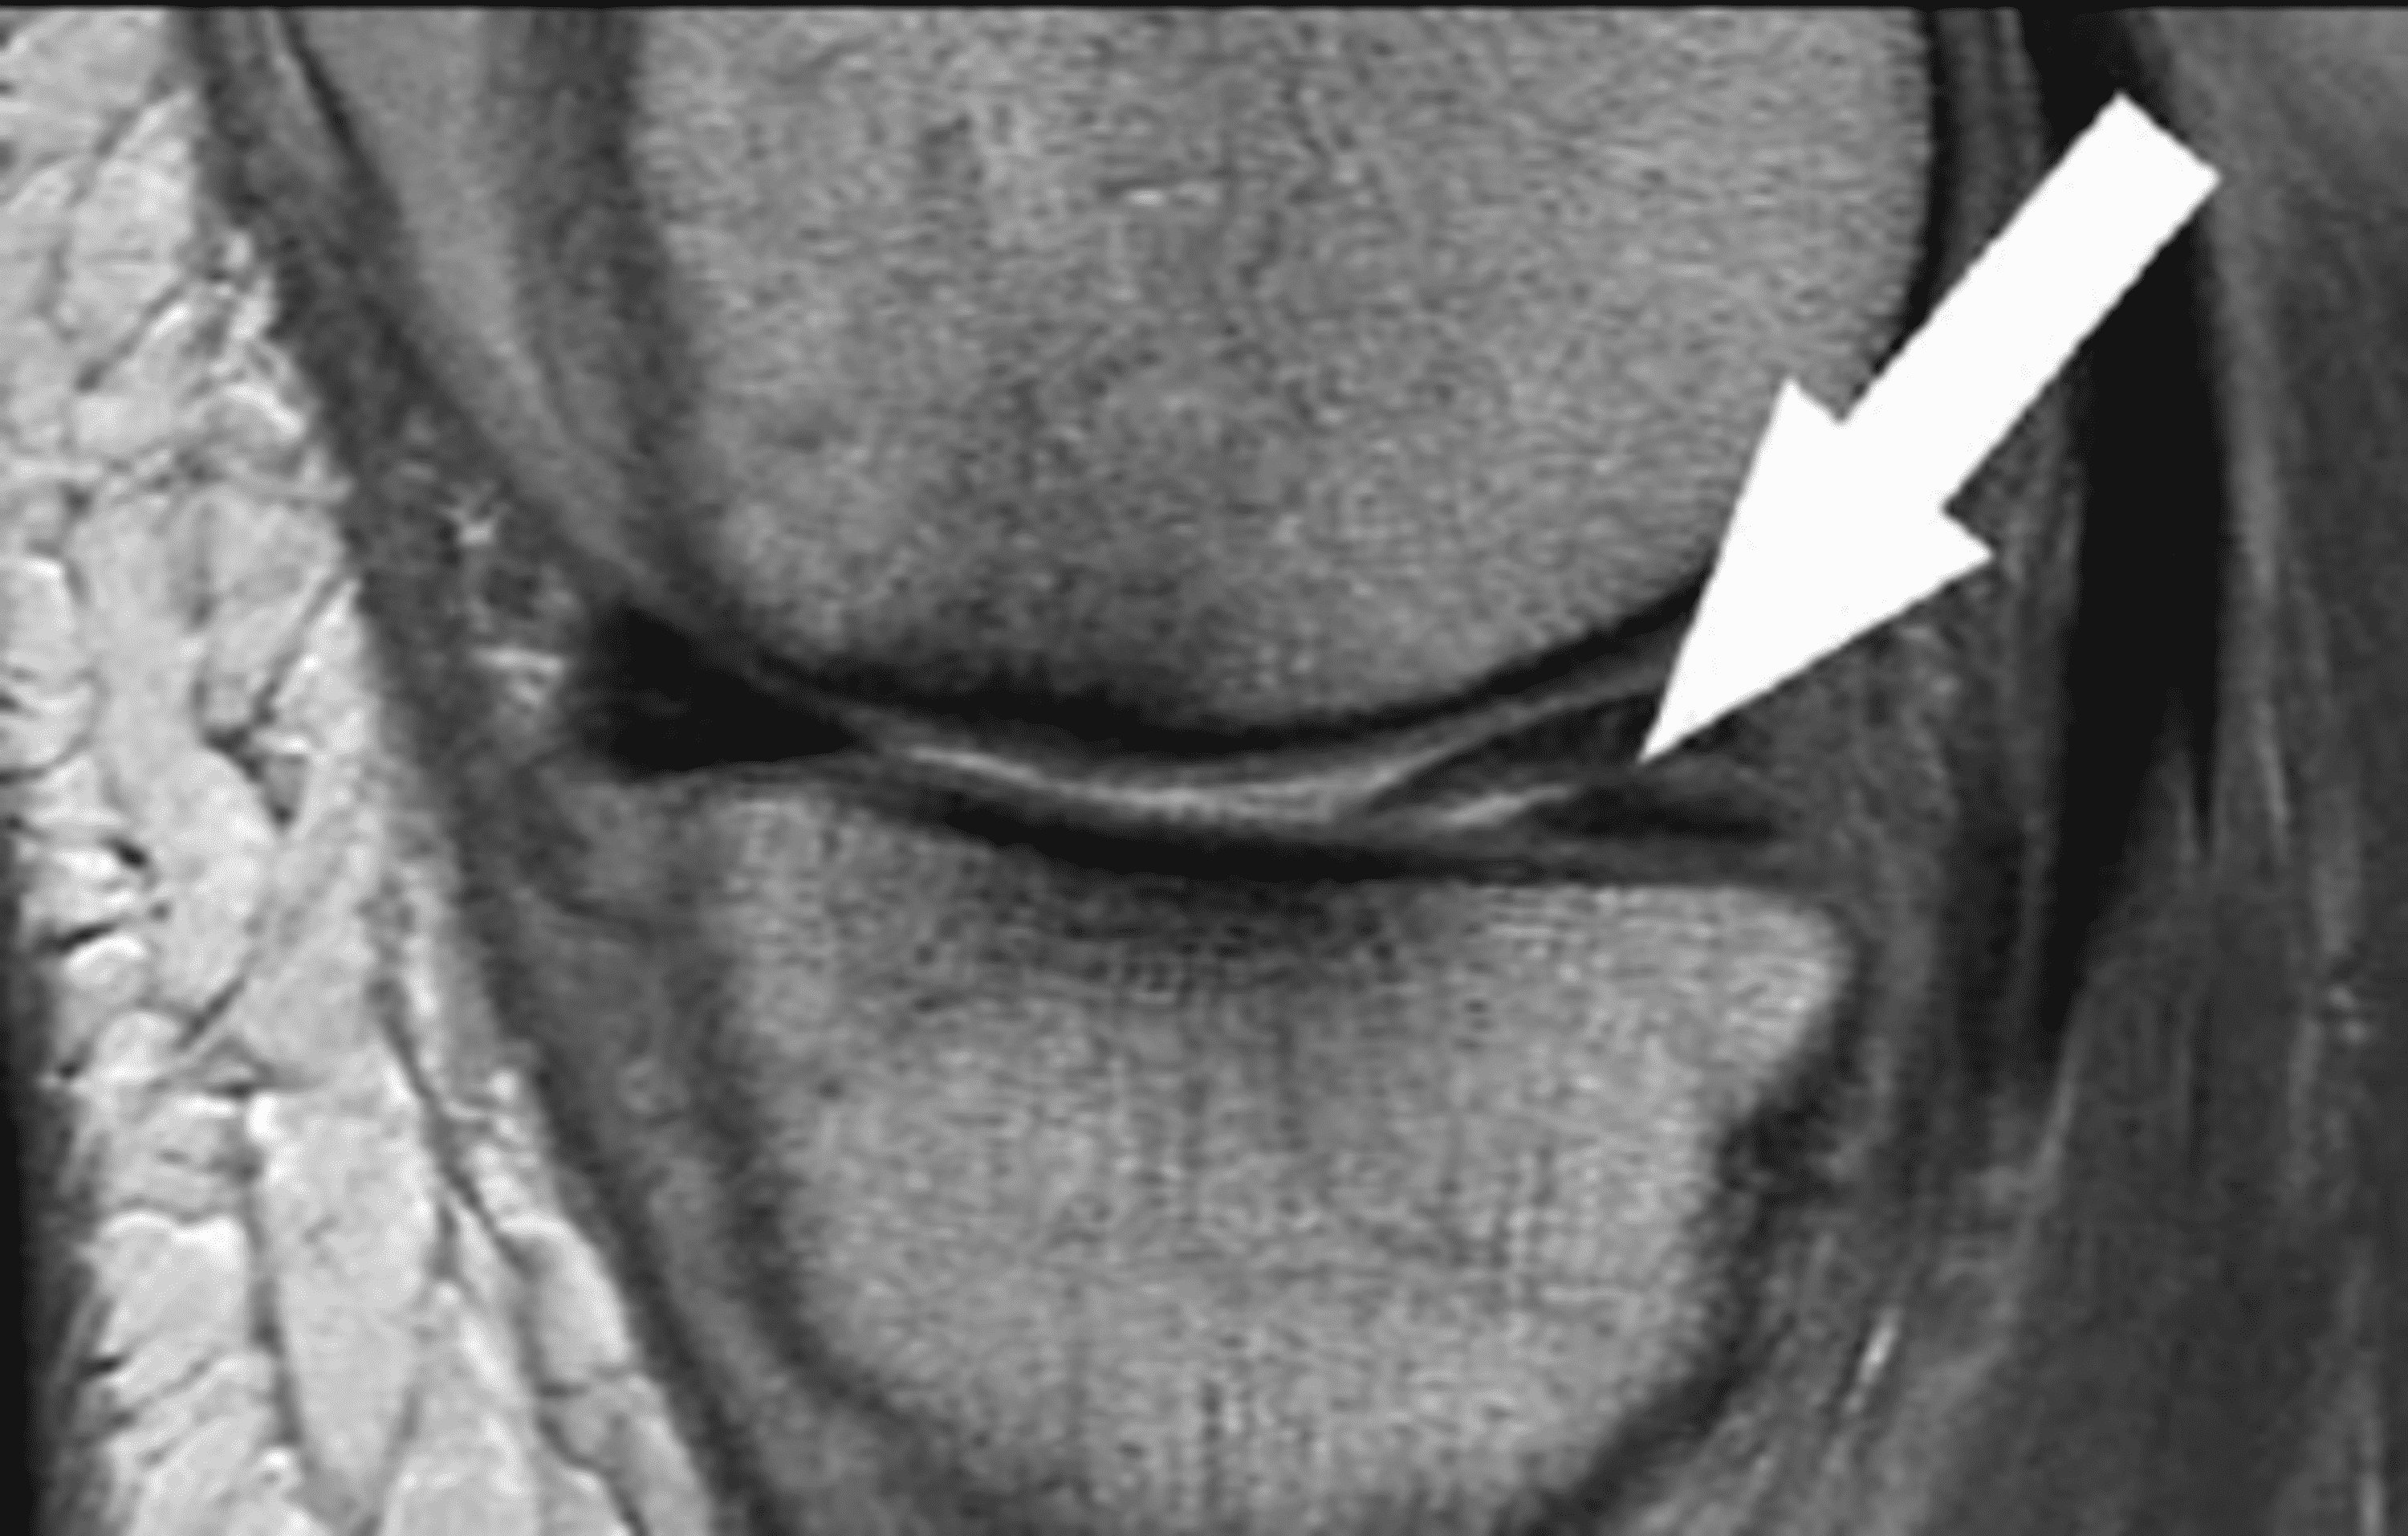

How to Read a Knee MRI for Meniscus Tears YouTube Therapeutic Ultrasound For Meniscus Tear ultrasound (us), magnetic resonance imaging (mri), and arthroscopic findings of a bucket handle medial. fig 5 ultrasound check and local anesthesia for a medial meniscal tear of the right knee (longitudinal view). at this stage, continuous ultrasound can be used to increase the blood supply in the healing tissue. thus, therapeutic ultrasound may be a beneficial. Therapeutic Ultrasound For Meniscus Tear.

Meniscus Tears on MRI Non surgical treatment options Therapeutic Ultrasound For Meniscus Tear at this stage, continuous ultrasound can be used to increase the blood supply in the healing tissue. thus, therapeutic ultrasound may be a beneficial modality to decrease pain and increase rom of the knee in an acutely. meniscal extrusion (me) under us can be a reliable metric to evaluate for meniscal root tears in knees with and. Therapeutic Ultrasound For Meniscus Tear.

From www.mri.melbourne